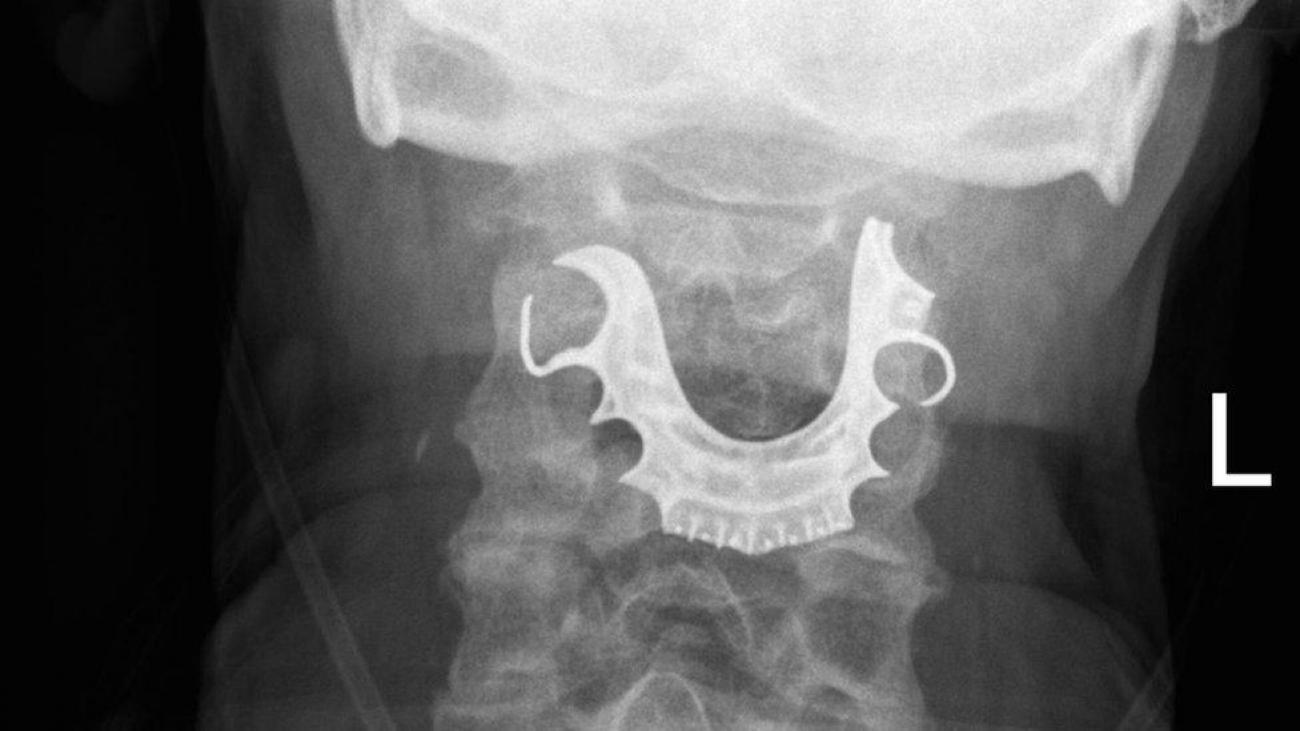

Kada se muškarac dva dana kasnije ponovo javio kod lekara, medicinsko osoblje pregledalo je grlo i glasne žice - i pronašlo polukružni predmet koji leži preko njih.

On je lekarima rekao da je za vreme operacije u bolnici izgubio protezu.